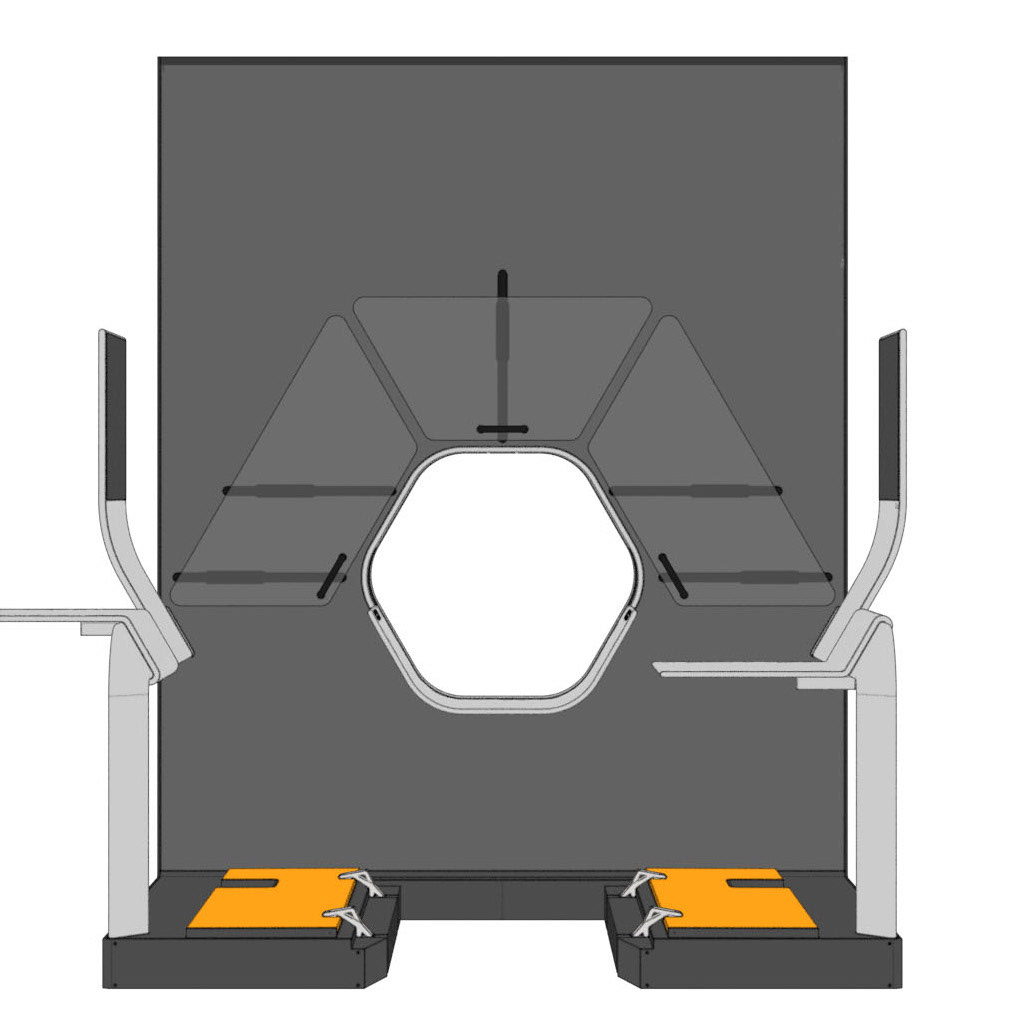

Auriga is an architecturally inspired CT device. The gantry extends to the ceiling and becomes a spatial installation. This takes away its massive “machine-character” and makes it part of the room. The gantry height is individually adapted to the given space - individuality becomes part of the product. In order to enable right- and left-handed working, the overall construction is symmetrical and intervention from both sides is equally possible.

The central design feature is the hexagonal gantry opening. It provides space for the lamps and displays. The large fronts of the gantry offer space for a display of different coloured patterns and animations, which visualize the radiation. These can be individually selected and adapted together with the overall height of the gantry. The patterns pick up on the hexagonal shape of the gantry opening and set it off. To protect the interventionists from radiation, lead glass panels and a radiation protection tray are installed. The sliding lead glass panels allow individual adaptation to the patient and the interventionists working space. The tray serves to protect the abdomen and offers a lot of foot space as well as a front leaning aid for a safe stand.

Due to the new position and height of the gantry opening, the isocenter is shifted upward compared to conventional CT units. In order for the physician to operate as usual in the isocenter, his platform must also be shifted upward by this height difference. A review in VR showed that a platform height of 15cm provides the optimal comfort for the interventionalist.

INTERFACES

For direct inspection of the CT scans, there is one large overview screen per side and a small detail screen inside the gantry. The control interface of the gantry is located inside the lower trough, which protects the abdomen of the interventionists from radiation. In addition, there is a foot pedal on the floor that allows hands-free activation of the CT imaging.